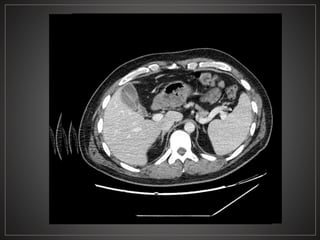

• #40 Serie de TC abdomen en fase portal, hacia topografia de coledoco se observa una lesion de morfologia redondeada, de bordes definidos, densidad liquido, con medidas de 59 × 53 × 41 ubicada entre la vesícula biliar la cual se encuentra colapsada y la cabeza pancreática.

• #47 Axial ventana tejidos blando fase portal, se observan multiples imágenes de morfología ovalada, de bordes definidos, hipodensa, correpondiente a quistes intrahepaticos y un quiste grande extrahepatico - tipo IVa

• #48 V-Dilataciones multiples o simples intrahepaticos (enfermedad de Caroli)